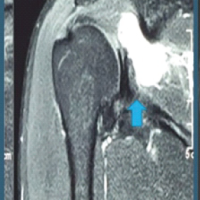

Case 5

A 70-year-old female with a long PFN presented with screw breakage at 5 months, requiring revision to total hip replacement (Fig. 5).

Figure 5: (a) 5 months post-operative anterior-posterior (A-P) view X-ray showing screw-breakage in pertrochanteric femur fracture of the left side fixed with short proximal femoral nail. (b) Post-operative A-P view X-ray showing total hip replacement done after implant removal.